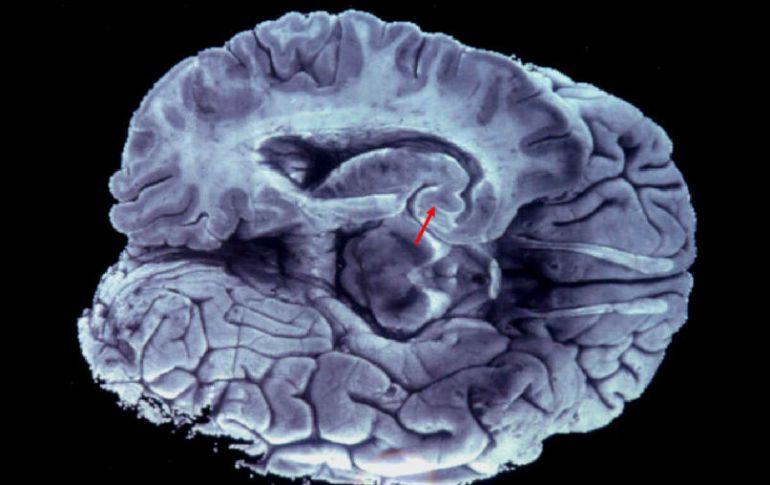

Tecnología | El proyecto está financiado con tres millones de euros anuales para los próximos años Bruselas inaugura instituto para investigar enfermedades del cerebro El proyecto está financiado con tres millones de euros anuales para los próximos cinco años, un monto aportado por la Fundación ULB Por: NTX 28 de marzo de 2013 - 12:54 hs La mayoría de las enfermedades del cerebro son mal comprendidas a día de hoy y no tienen tratamiento. ARCHIVO / BRUSELAS, BÉLGICA (28/MAR/2013).- La Universidad Libre de Bruselas (ULB) inauguró hoy aquí su Instituto de Neurociencias (UNI), un centro de investigación multidisciplinar sobre el cerebro que reune a más de 150 investigadores de 17 laboratorios y cuatro disciplinas. El proyecto está financiado con tres millones de euros anuales para los próximos cinco años, un monto aportado por la Fundación ULB que, sin embargo, pretende encontrar fuentes de financiación adicionales, como ayudas de la Unión Europea o del gobierno belga. El objetivo es reunir los conocimientos de las áreas de neurofisiología, neuro-imagen y las neurociencias moleculares y cognitivas para buscar respuestas a enfermedades del sistema nervioso aún mal conocidas y que afectan a 2.9 millones de personas sólo en Bélgica. "La mayoría de las enfermedades del cerebro son mal comprendidas a día de hoy y no tienen tratamiento", señaló el profesor Serge Goldman, uno de los responsables del proyecto. "Es necesario un nuevo enfoque para comprender tanto el desarrollo del cerebro como la degeneración de sus funciones cognitivas que conducen a enfermedades como Alzheimer o Parkinson", apuntó. La cooperación entre las diversas disciplinas dedicadas a la investigación del cerebro, genética, psicología, neurobiología y neurología, será reforzada con la realización de seminarios y la adquisición de equipamientos tecnológicos para uso común. "Gracias a los proyectos de sinergia, nuestro instituto deberá alcanzar una masa crítica de excelencia y garantizar a la ULB una mejor visibilidad internacional", confió el director del UNI, Pierre Vanderhaeghen. Temas Investigación científica Ciencia médica Cerebro Alzheimer Mal de Parkinson Lee También Detalles sobre la esquizofrenia, la experiencia de "voces" internas Conmociones cerebrales, la cuarta lesión más frecuente en partidos de la Conmebol Estudio chino revela una mutación que eleva riesgo de alzhéimer ¿Cómo se forman los recuerdos en la mente? Recibe las últimas noticias en tu e-mail Todo lo que necesitas saber para comenzar tu día Registrarse implica aceptar los Términos y Condiciones